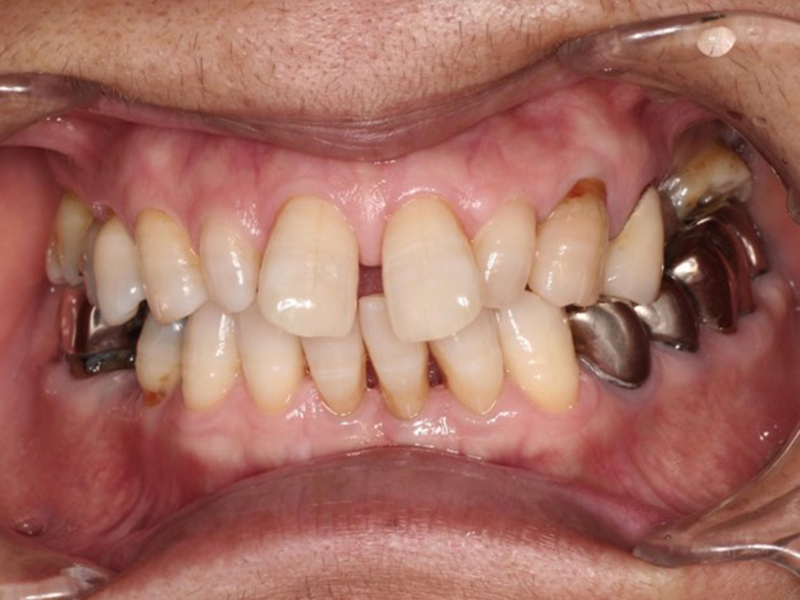

▼ ケース6.矯正的挺出

矯正開始前

矯正開始

矯正終了

補綴終了

矯正開始前、矯正終了時、補綴終了